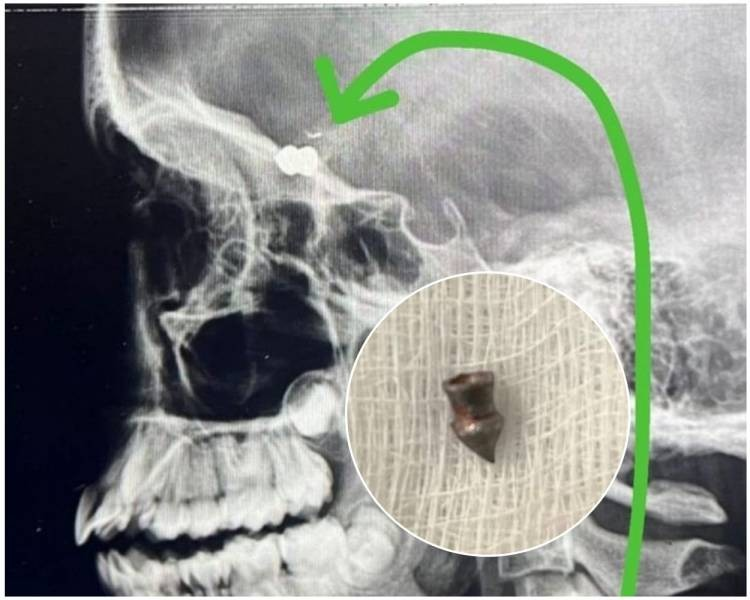

Desesperada, a criança começou a pedir ajuda e foi levada para o hospital da cidade, onde passou por exames e foi constatado que ela estava com um projétil próximo ao globo ocular.

Os médicos que operaram a criança, informaram que o “chumbinho” poderia ter atingido três regiões fatais na cabeça da menina: o globo ocular, que poderia deixá-la cega; uma artéria ou o próprio cérebro, o que levaria a morte.